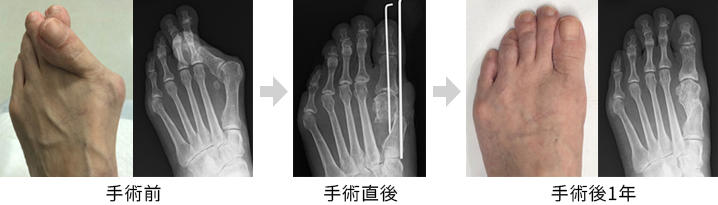

外反母趾

外反母趾については、3,000例を超える手術実績がある第一人者であり、外反母趾に対する手術の効果と限界について熟知している須田康文病院長が診療を行います。

外反母趾の手術「DLMO法」

「DLMO(デルモ)法」は、外反母趾の手術方法の一つで、軽度から中等度の外反母趾に対して適用される術式で、親指の付け根の骨を切り、変形を修正し、ピンで固定するシンプルな方法で、手術時間も短く、術後の痛みも比較的少ないため、患者様の負担が小さい手術となります。